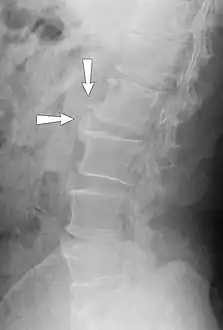

X-ray showing osteophytes of spondylosis of the lumbar spine